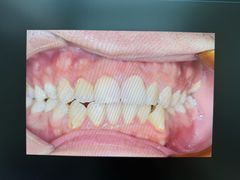

• 牙博士口腔品牌连锁(杨浦店)

• -牙博士口腔品牌连锁(杨浦店)

wenwenqing | 25-05-31